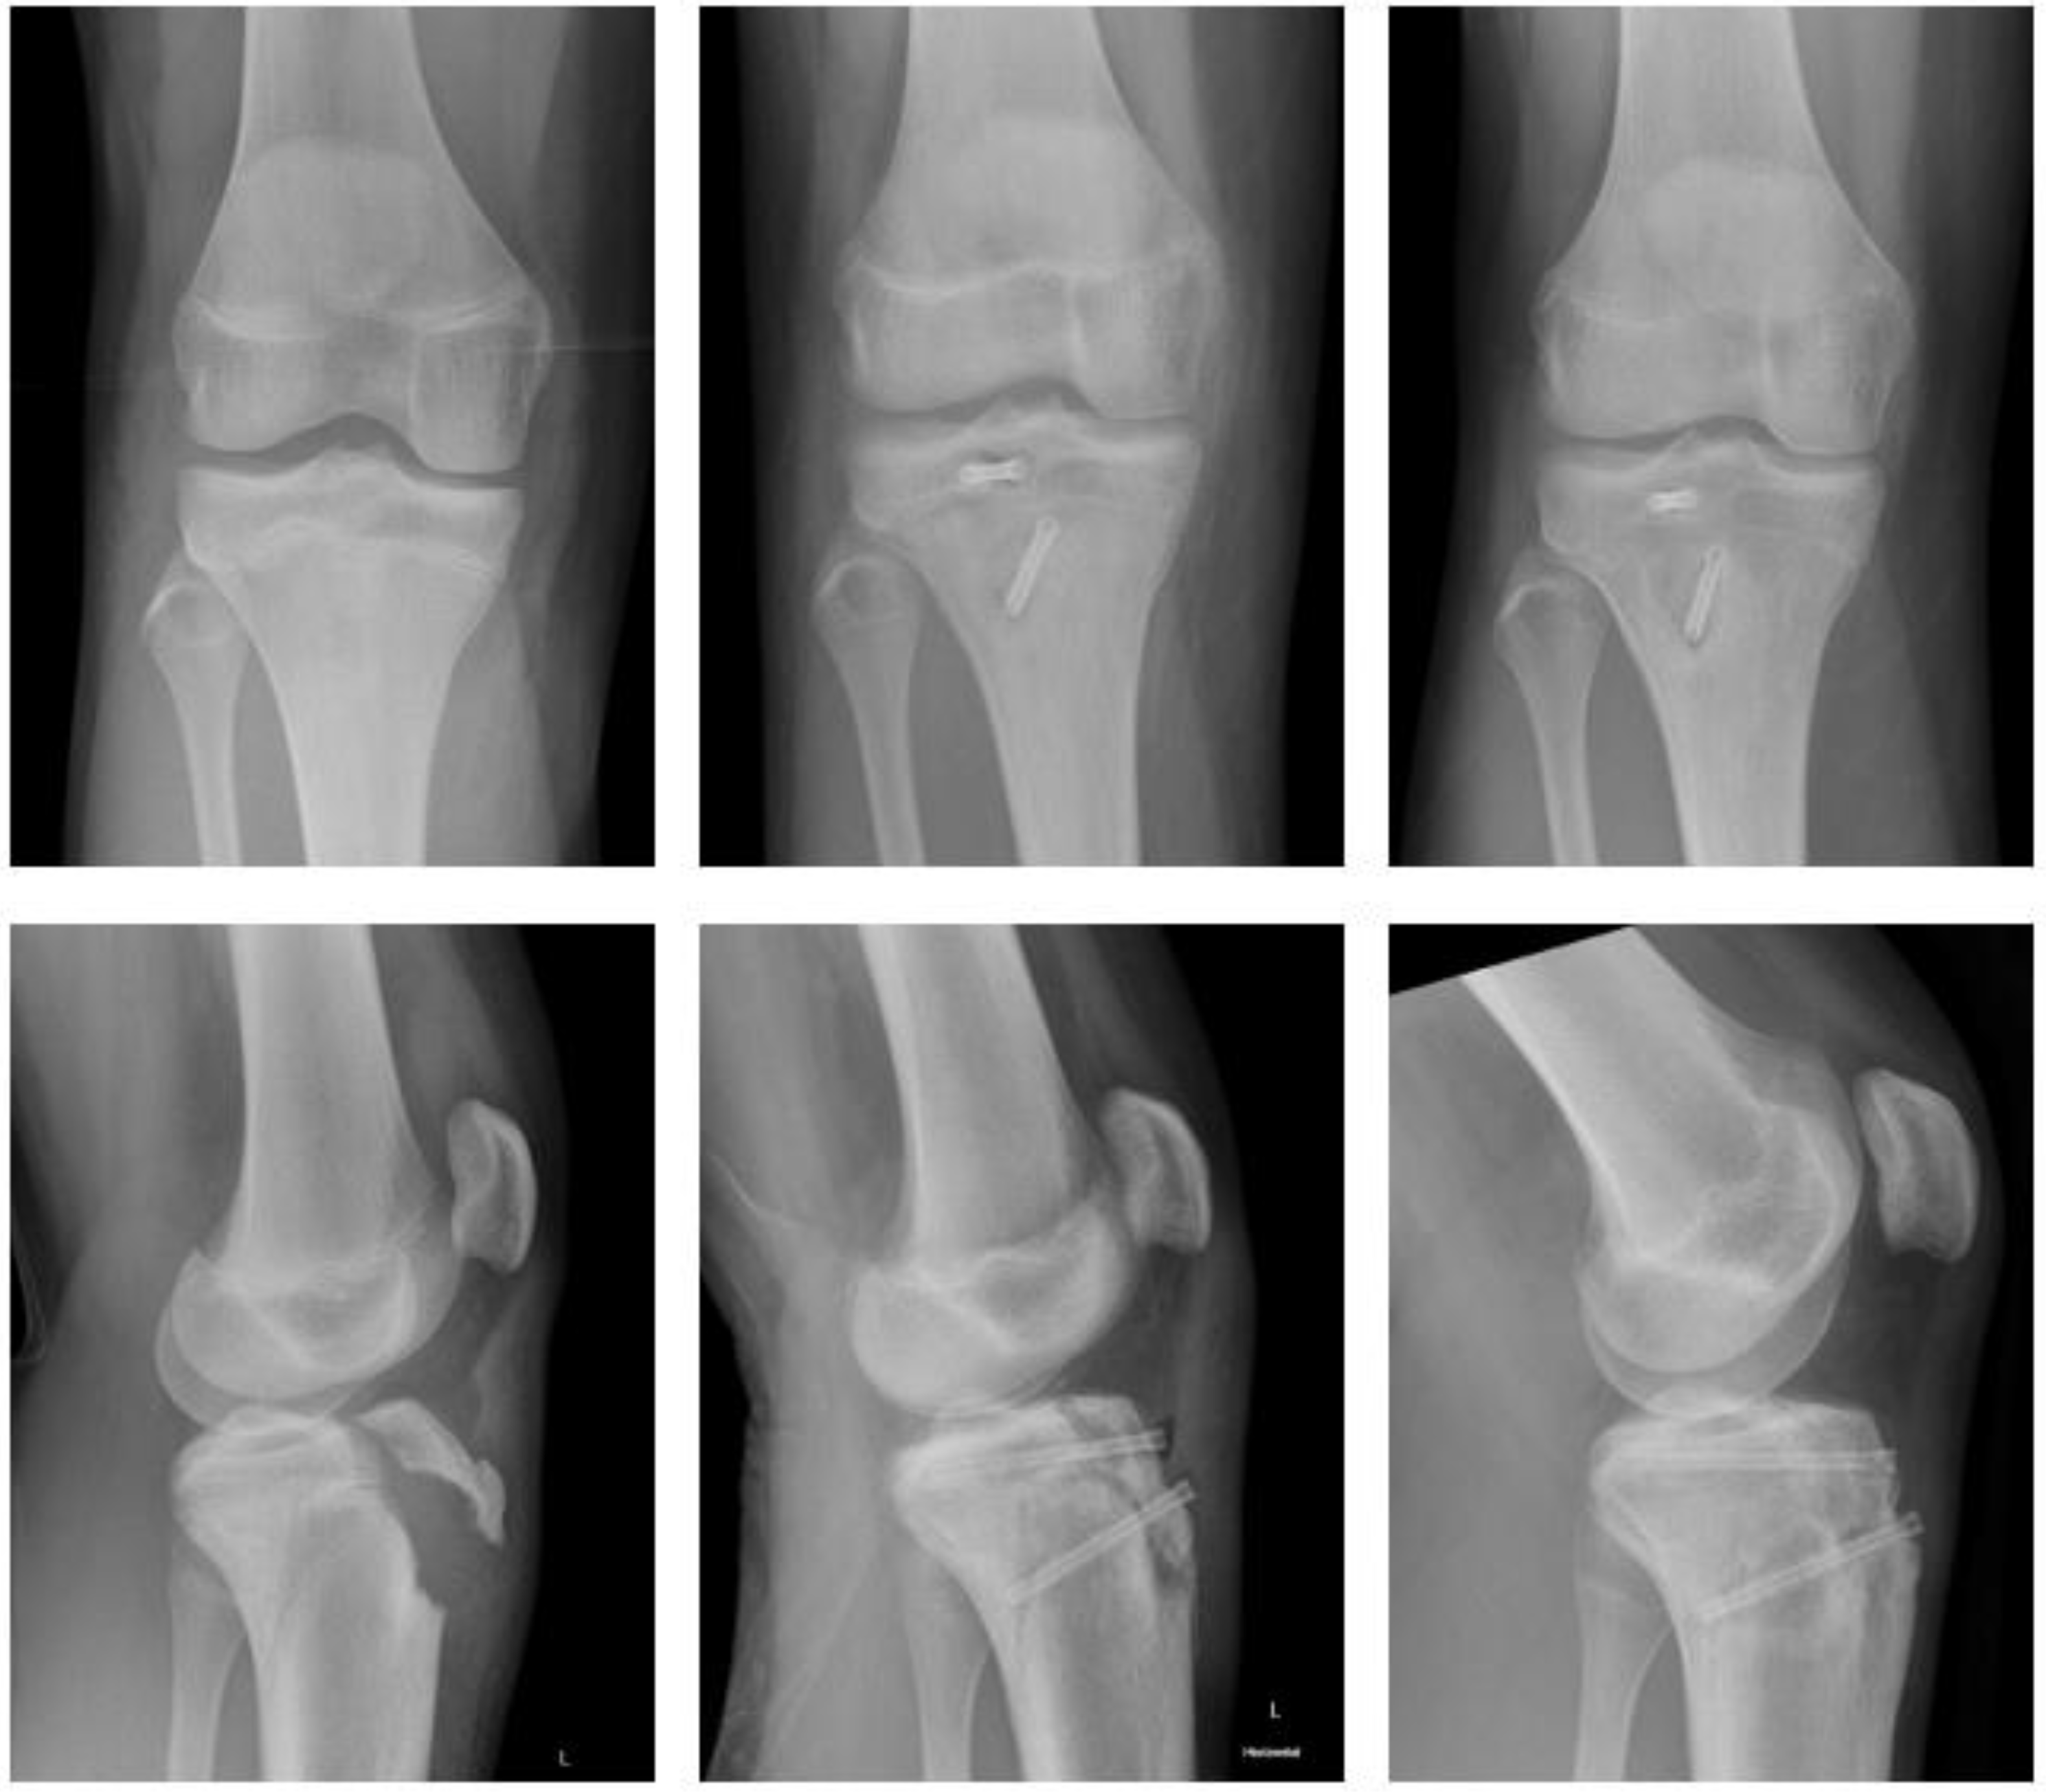

2.4.1. Fracture of the Tibial Tuberosity